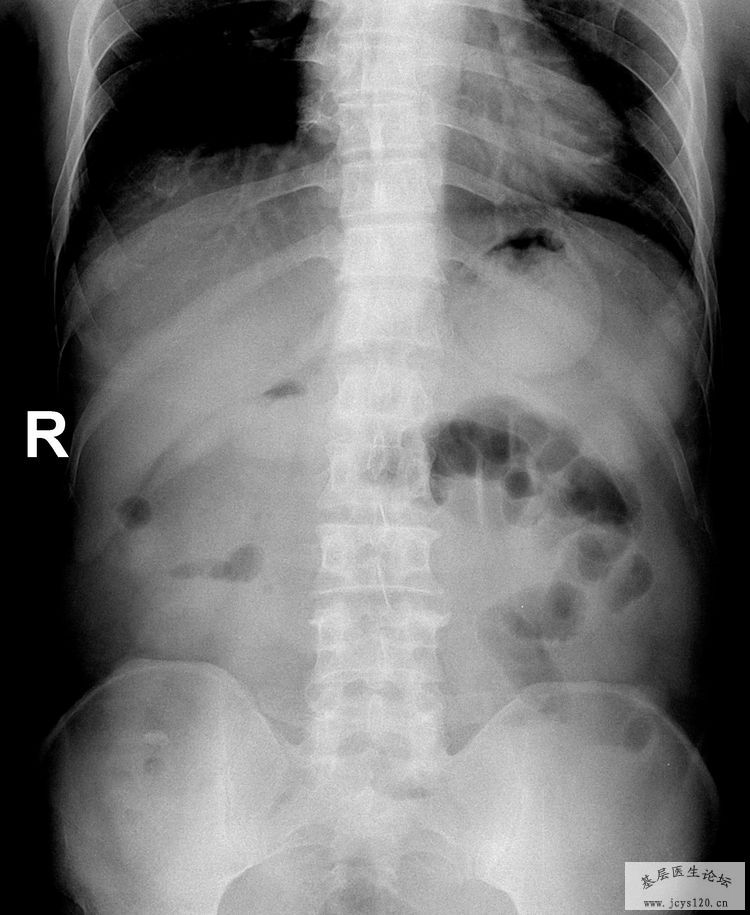

高度怀疑肠梗阻和胃穿孔的可能性。 阅读全文>